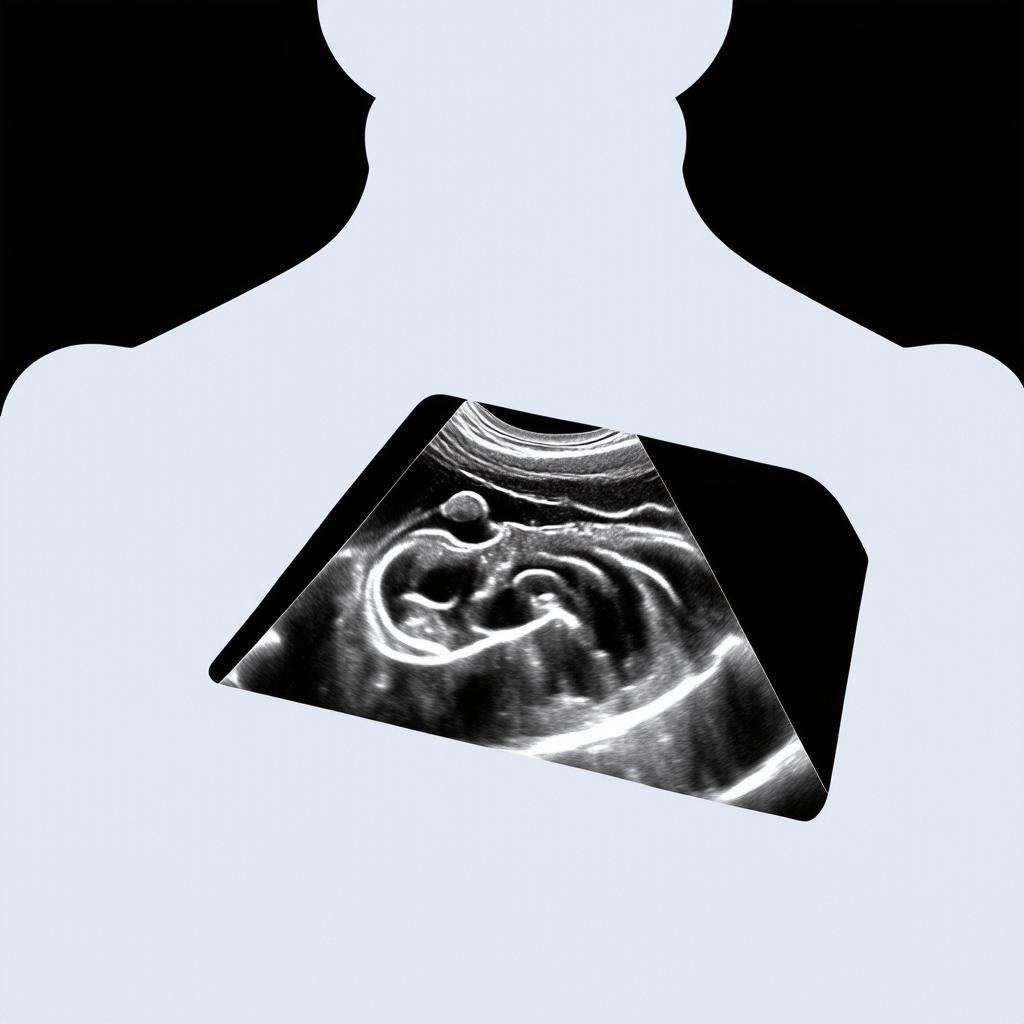

Ультразвуковое исследование назначается при наличии различных симптомов и жалоб, а также в рамках профилактического обследования. Среди основных показаний можно выделить боли в животе различной локализации, нарушения пищеварения, изменения в анализах крови и мочи, подозрение на заболевания внутренних органов. УЗИ является обязательным компонентом диспансеризации и рекомендуется для регулярного прохождения даже при отсутствии жалоб. Особое значение ультразвуковая диагностика имеет в акушерстве для наблюдения за развитием беременности и состоянием плода. Также УЗИ широко используется для контроля эффективности лечения и динамического наблюдения за выявленными ранее патологиями.

- Наблюдение за течением беременности

Современная ультразвуковая диагностика постоянно развивается, появляются новые технологии, значительно расширяющие диагностические возможности. В нашей клинике используется оборудование экспертного класса, оснащенное передовыми технологиями. Цветное допплеровское картирование позволяет оценивать кровоток в сосудах и выявлять нарушения кровоснабжения органов. Трехмерное и четырехмерное УЗИ создает объемные изображения, что особенно ценно в акушерстве для оценки развития плода. Эластография - инновационный метод, позволяющий оценивать жесткость тканей и дифференцировать доброкачественные и злокачественные образования. Контрастное усиление улучшает визуализацию сосудов и патологических очагов.